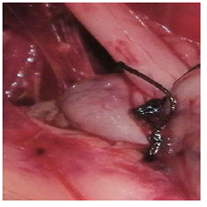

Our results support the rabbit as a suitable animal model for the teaching and practice of Nissen fundoplication by laparoscopy. However, it might not be appropriate for human surgeons to develop the more complex skills required to master the technique, due to anatomical differences between both species (Table 2). In effect, for early learning stages, the rabbit was an excellent model in which to perform knots and the periesophageal wrapping cuff using laparoscopic instruments (Figs. 3 -7). Formation of knots is one of the most difficult elements of the technique in human surgery. Consequently, preliminary training with simulators is recommended.1,3 Indeed, ligation of gastric short vessels is considered to be the most difficult maneuver of this surgery.33 In addition, ligation of the short vessels is essential for fundoplication because it can decrease morbidity of patients undergoing laparoscopic surgery.34 However, it is worth mentioning that there is a Nissen-Rossetti procedure in which ligation of the short gastric vessels is not necessary.6 Moreover, an easier and faster Nissen fundoplication technique allows to avoid the cutting of the short gastric vessels altogether.35